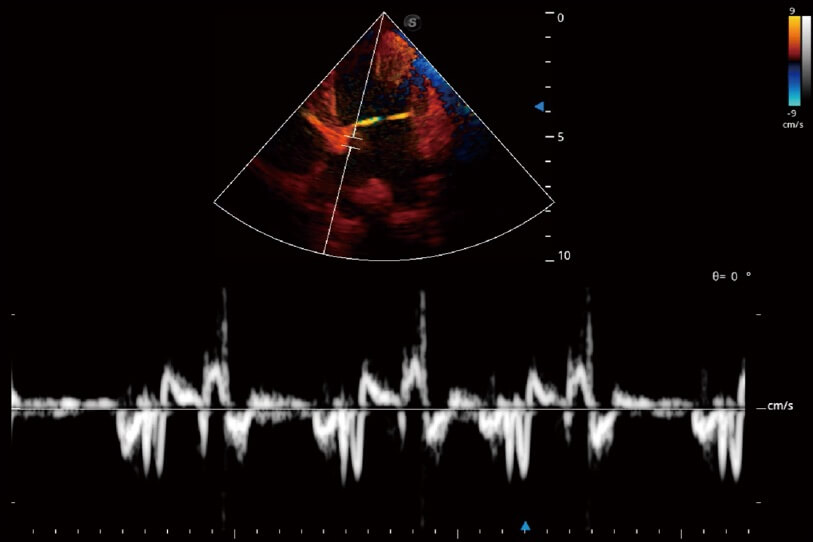

實時用顏色表示心肌組織運動,觀察和定量組織的運動情況,對快速檢測與評估心肌的灌注和活性、電傳導(dǎo)及心肌收縮和舒張功能等均能提供重要的診斷信息。